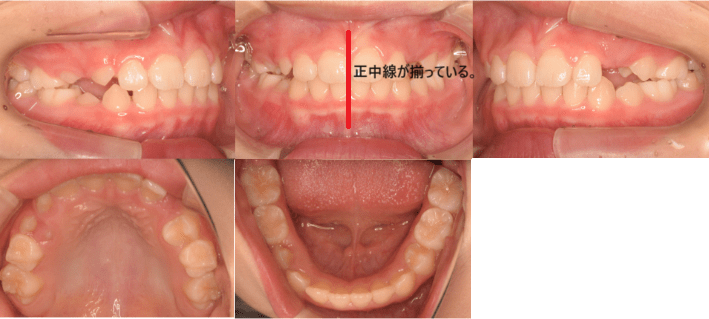

治療例➁7歳4ヶ月

| 初診時年齢 | 7歳4ヶ月 |

| 主訴 | 前歯の隙間が気になる |

| 診断 | 正中線の不一致と叢生を伴う過蓋咬合 |

| 抜歯の有無 | 非抜歯 |

| 治療内容 | マウスピース型カスタムメイド矯正歯科装置(製品名インビザライン完成物薬機法外)を使用して主訴である前歯の隙間を閉じると同時に永久歯の生える場所を確保すると同時に、前歯のかみ合わせが深い過蓋咬合についても前歯の重なりがなくなるように改善しました。 |

| 治療期間 | 9カ月 通院回数8回 |

| リスク | 矯正歯科装置を付けた後しばらくは違和感、不快感、痛みなどが生じることがあります。 治療中は矯正歯科装置が歯の表面に付いているため食物が溜りやすく、また歯が磨きにくくなるため、むし歯や歯周病が生じるリスクが高まります。 歯を動かすことにより歯根が吸収して短くなることや歯肉がやせて下がることがあります。 |

| 費用 | 40万円 |

【治療前】

【治療後】